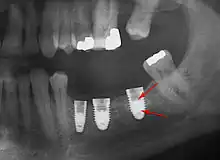

Long-term failures are due to either loss of bone around the tooth and/or gingiva due to peri-implantitis or a mechanical failure of the implant. Because there is no dental enamel on an implant, it does not fail due to cavities like natural teeth. While large-scale, long-term studies are scarce, several systematic reviews estimate the long-term (five to ten years) survival of dental implants at 93–98 percent depending on their clinical use.[2][3][4] During initial development of implant retained teeth, all crowns were attached to the teeth with screws, but more recent advancements have allowed placement of crowns on the abutments with dental cement (akin to placing a crown on a tooth). This has created the potential for cement, that escapes from under the crown during cementation to get caught in the gingiva and create a peri-implantitis (see picture below). While the complication can occur, there does not appear to be any additional peri-implantitis in cement-retained crowns compared to screw-retained crowns overall.[75] In compound implants (two stage implants), between the actual implant and the superstructure (abutment) are gaps and cavities into which bacteria can penetrate from the oral cavity. Later these bacteria will return into the adjacent tissue and can cause periimplantitis.